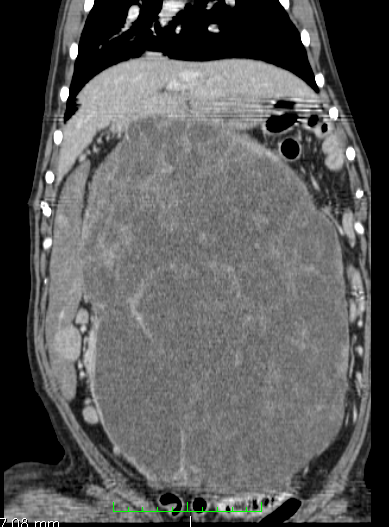

Buster is an 8 year old retriever who started to go off his food. Clinical examination soon identified a very large abdominal mass which was thought to be either hepatic or splenic in origin. Computerised Tomography (CT) was used to assess the organ of origin and to stage the tumour (i.e. assess for any metastasis) and no abnormalities were found other than a nodular, massively enlarged spleen.

Sagital and coronal reconstructed CT images showing a massive splenic mass occupying the majority of the dog’s abdominal cavity